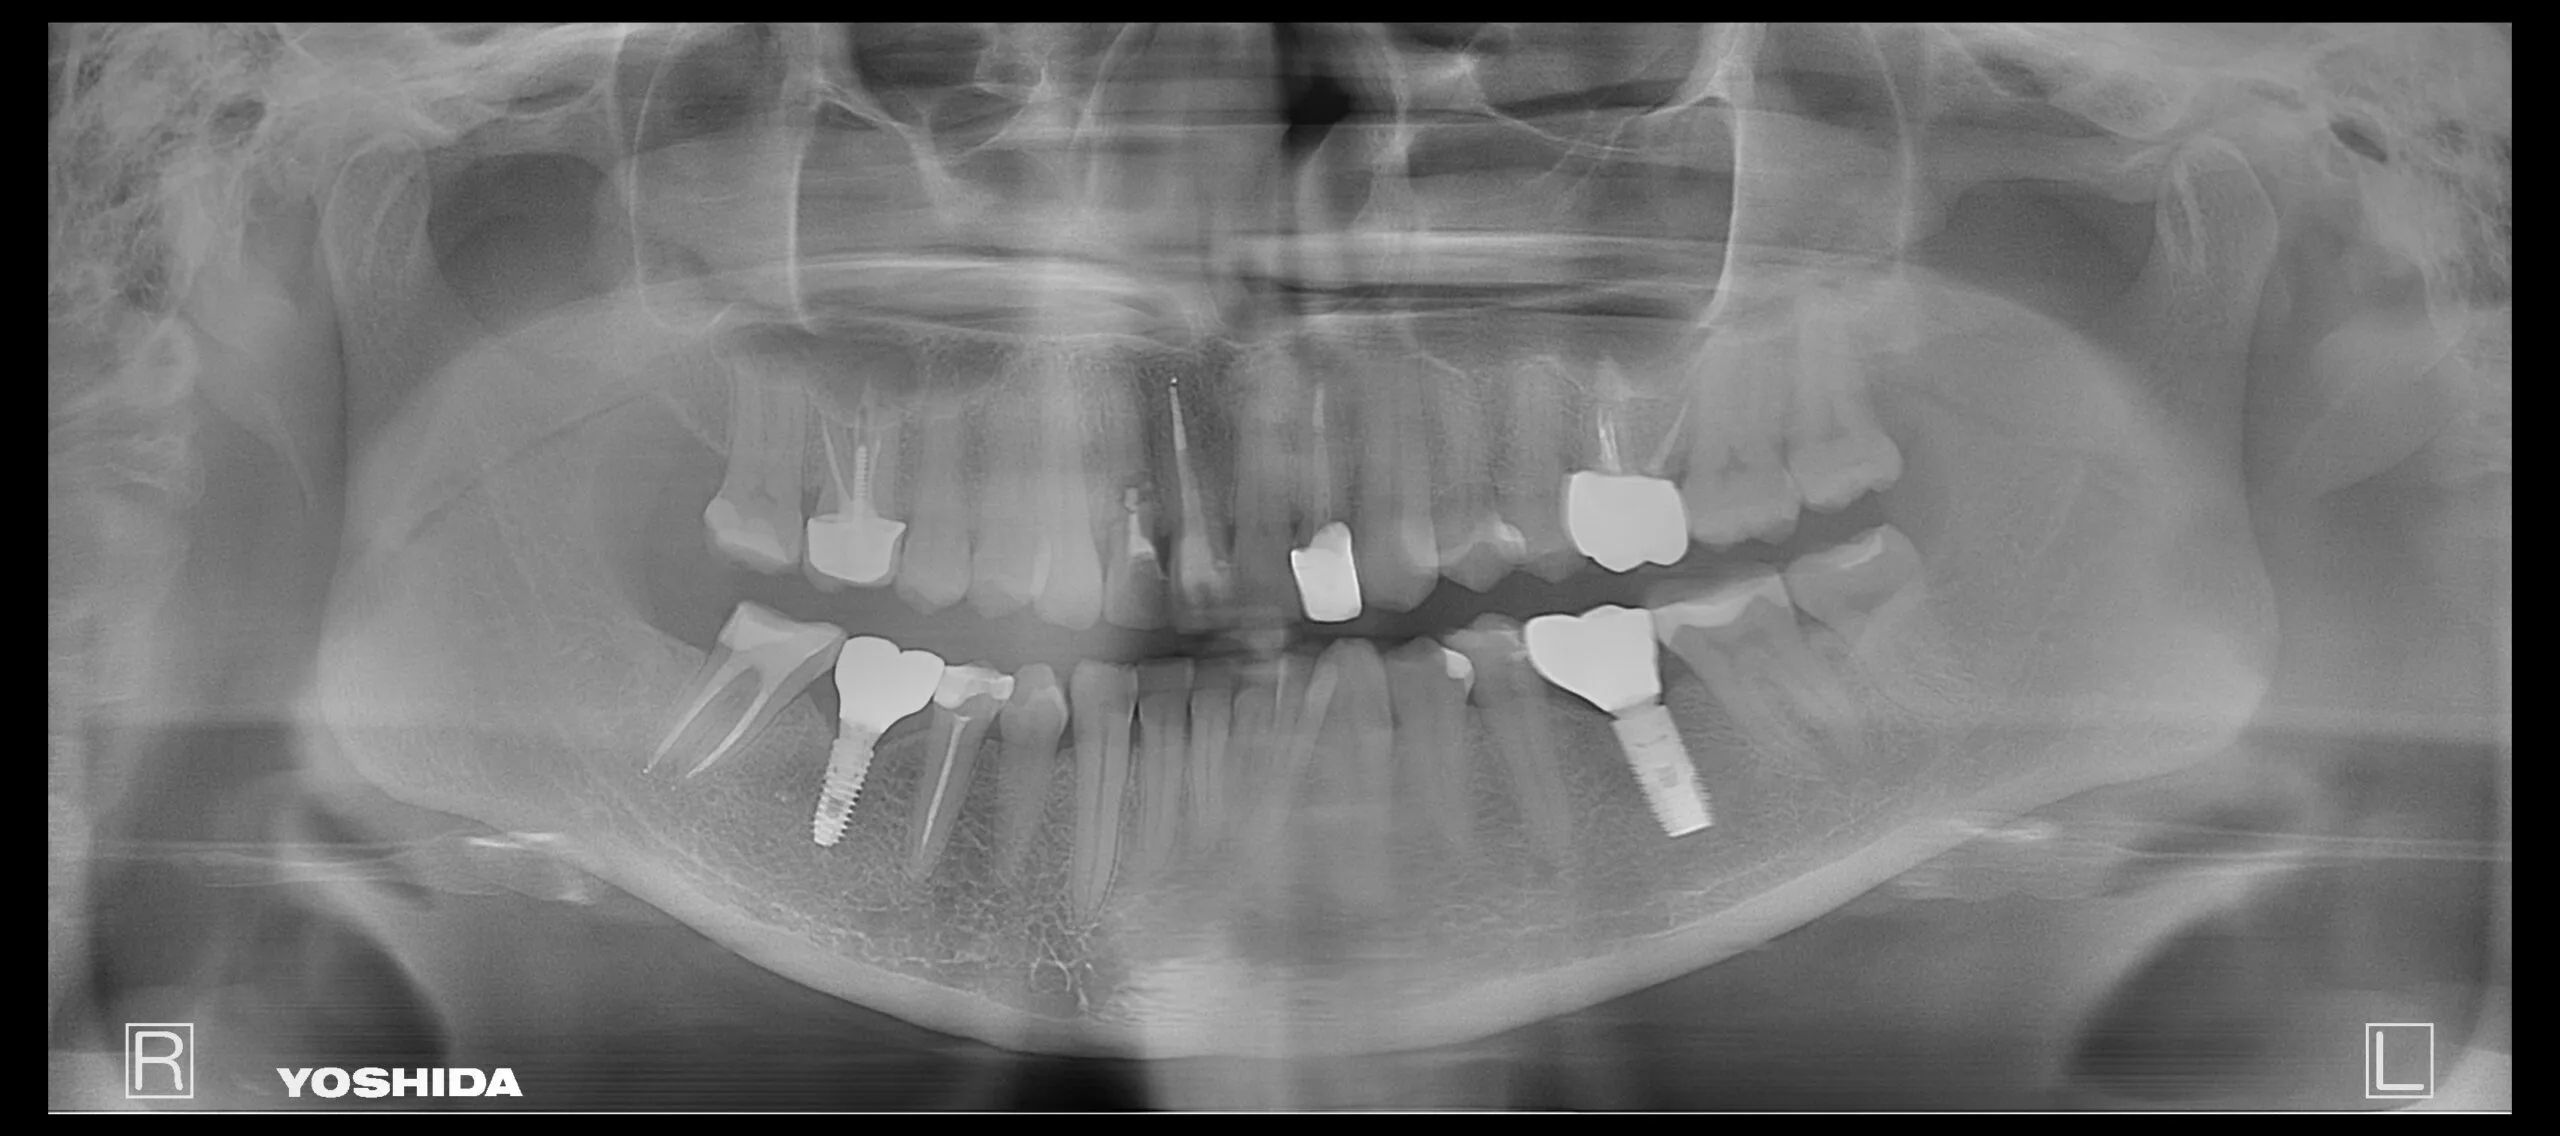

Protezavimas ant implantų

Pacientė kreipėsi dėl skilusių 12 ir 22 dantų šaknų, todėl jautė skausmą ir reikėjo skilusius dantis pašalinti. Pašalinus, buvo įsriegti implantai, jiems prigijus, suformuotos gijimo galvutės ir pritaikyti laikini vainikėliai ant implantų, kad pacientė priprastų prie naujų dantų formos ir pritaikytos spalvos. Net laikinų restauracijų sunku atskirti nuo natūralių dantų ir galime pilnavertiškai džiaugtis savo dantų būkle.